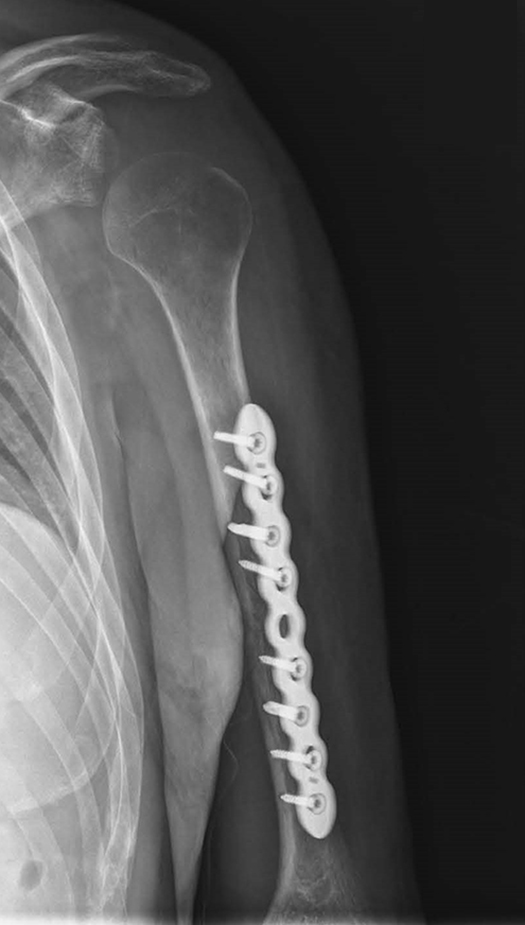

Joe también sufrió una lesión cerebral traumática leve que resultó en pérdida de memoria, concentración deteriorada y cambios de personalidad. También sufrió dolor crónico en la cadera izquierda y la parte baja de la espalda. Más tarde, aproximadamente 18 meses después de la colisión, se le diagnosticó un desgarro del labrum en el hombro izquierdo. Mucho más tarde, poco antes de la fecha del juicio, se le diagnosticó un presunto síndrome de la salida torácica (dolor causado por una costilla que atrapa un nervio de la columna torácica).

Joe fue trasladado a un hospital local en ambulancia y luego a Spokane, donde estuvo hospitalizado durante dos días. Tras el alta, estuvo mayormente confinado a una cama de hospital y tuvo que quedarse con su madre durante varias semanas para que ella pudiera cuidarlo. Su esposa era estudiante de medicina de primer año. La madre de Joe tuvo que ayudarle a hacer todo, ya que apenas podía moverse sin un dolor intenso.

Joe llevó una férula y un cabestrillo, y más tarde una abrazadera en el brazo izquierdo durante varias semanas. También llevó una bota ortopédica en el pie izquierdo y un zapato postoperatorio en el pie derecho durante seis semanas.

Se le diagnosticó el cartílago desgarrado en el hombro y se sometió a una segunda cirugía, esta vez ambulatoria, para volver a unir el cartílago desgarrado. Después de esta cirugía, no pudo volver a conducir camiones trituradores como había hecho la mayor parte de su vida laboral. Tenía un título de bachillerato.